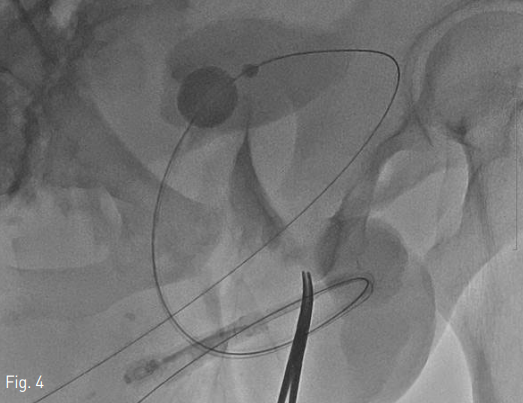

양측 속장골동맥과 그 분지들에서 기인하는 동맥 출혈에 대한 색전술을 시행한 후 요도재배열술을 시작함. 먼저 이전 거치되어 있던 요도관을 제거하고 5 Fr catheter (KMP, Cook, Bloomington, Indiana)를 요도 입구에 삽입한 다음, 2% 리도카인 10mL를 카테터 내로 주입하고 역행성 요로 조영술을 시행하였을 때 전립선-막양부 요도 파열과 조영제 유출 소견이 확인됨 (Fig. 2). 0.035-inch guidewire (Terumo, Tokyo, Japan)와 카테터를 이용하여 손상된 요도를 지날 때까지 조정하였으나, 조영제로 확인하였을 때 완전 파열된 요도의 바깥 자유공간으로 카테터가 반복적으로 나가는 양상임. 이에 환자의 치골상방 부위에서 초음파 유도하에 21 gauge Chiba needle로 방광을 천자하였음. 0.035-inch guidewire (Terumo)와 5 Fr catheter (KMP, Cook)를 방광 내에 거치시키고 이전 혈관조영술로 인한 조영제를 흡인, 생리식염수로 희석시켜 시야를 확보하였음. 그 후 guidewire와 카테터를 이용하여 순행성 요로의 진관강 (true lumen)을 찾기 위한 조정을 하였으나 역시 많은 확률로 완전 파열된 요도의 바깥 자유공간으로 나가는 양상임. 이에 이전 역행성 요로로 넣어 놓은 카테터를 경계표 (landmark)로 삼아 전후상, 경사상 영상을 확인하면서, 치골 상부 방광루를 통한 순행성 guidewire를 파열된 부분을 지나, 전부요도의 진관강을 통해 바깥요도구멍으로 통과시키는데 성공함 (Fig. 3). Guidewire의 through-andthrough technique으로 치골상부로부터 바깥요도구멍까지의 경로를 확보한 상태로, 카테터를 바깥요도구멍에서 치골상부까지 삽입하고 guidewire의 soft tip 과 hard tip의 방향을 바꾸었음. 바깥요도구멍쪽으로 나와 있는 guidewire의 hard tip쪽으로, 미리 끝 부분에 18 gauge 바늘로 구멍을 내어 놓은 16 Fr 요도관을 삽입하여 방광 내에 거치하는데 성공함 (Fig. 4).

Fig 4

A 16 Fr Foley catheter was inserted into the bladder over the guidewire (through-and-through technique).